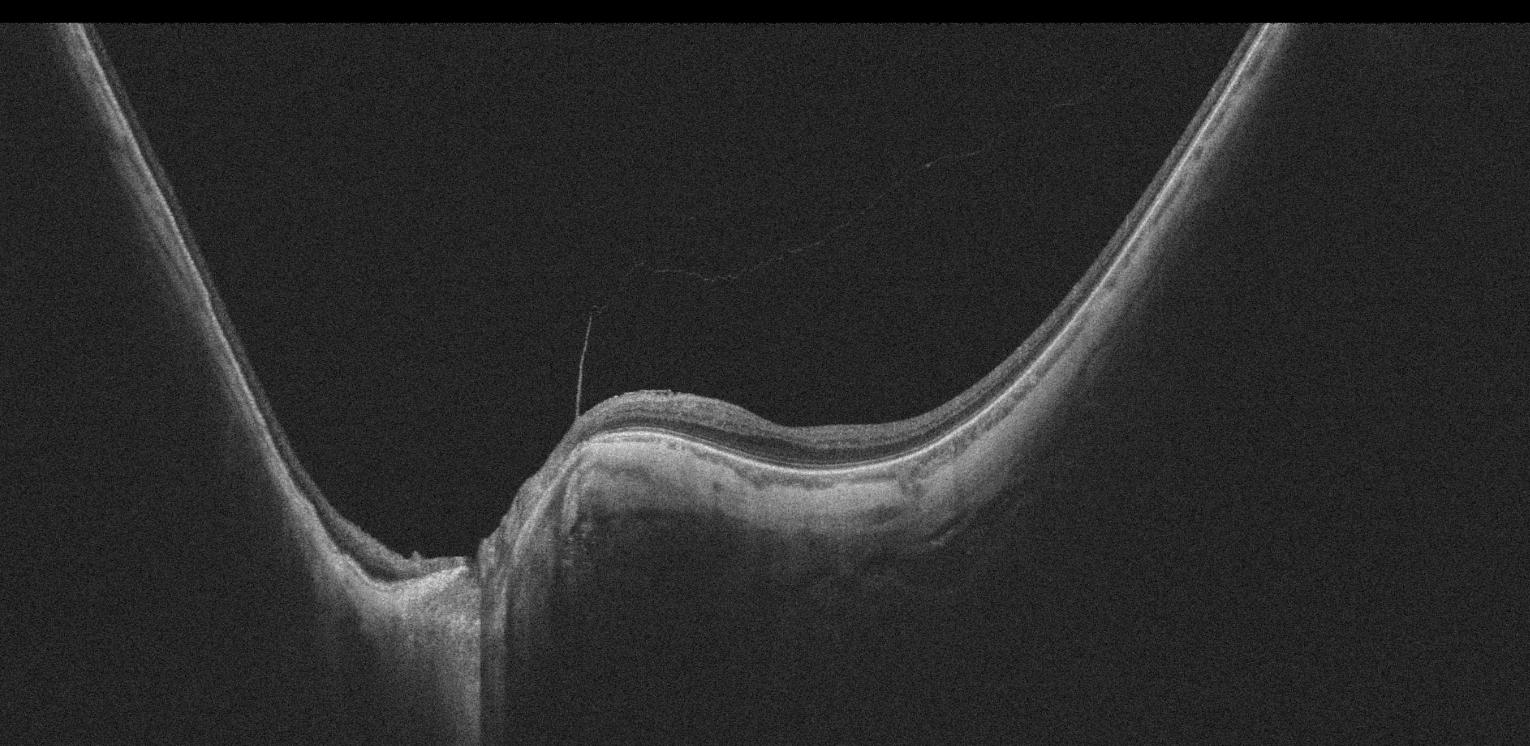

OCT Intalight montrant un staphylome myopique péripapillaire

OCT Intalight — Staphylome myopique péripapillaire (IPO Paris)